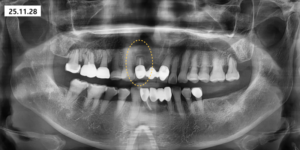

이후 현재까지 8년간

정기적인 경과 관찰을 진행하고 있습니다.

장기적인 추적 관찰 기간 동안

염증의 재발이나 추가적인 문제는

전혀 발생하지 않았고

치아는 안정적으로 잘 유지되고 있습니다.